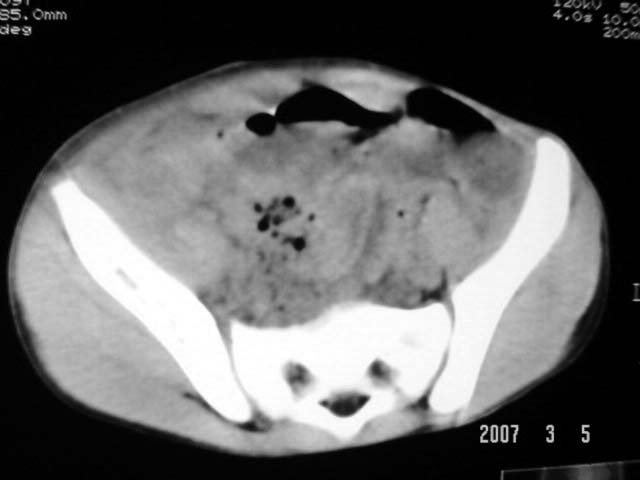

以下是引用dyqct在2007-3-5 10:28:00的发言:[br]右髂窝肿块。[br][br][br][br]